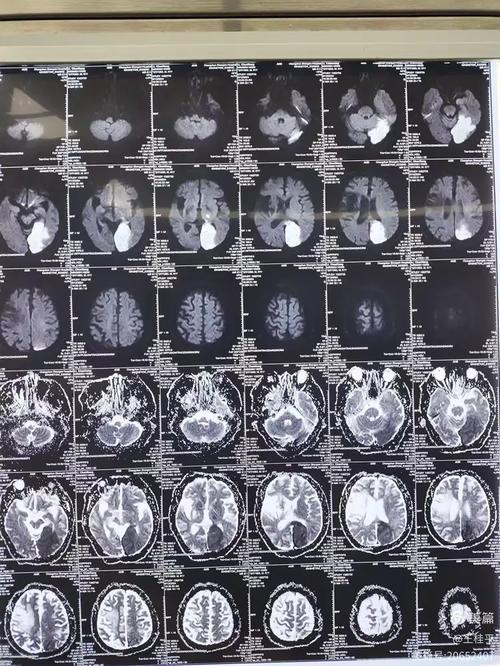

(图片来源网络,侵删)

检查方法:脑CT(计算机断层扫描)

- 是什么? CT是一种利用X射线来生成大脑详细图像的检查,它可以快速、清晰地显示大脑的结构,帮助医生判断是否存在出血、肿瘤、梗塞等问题。

- 在脑梗中的作用: CT是诊断急性脑卒中的首选和最紧急的检查,它的主要作用是“排除脑出血”,因为脑梗和脑出血的治疗方法完全相反,在用药前必须明确是哪种情况,新鲜的脑梗塞在CT上早期可能看不出来,但可以排除更危险的脑出血。